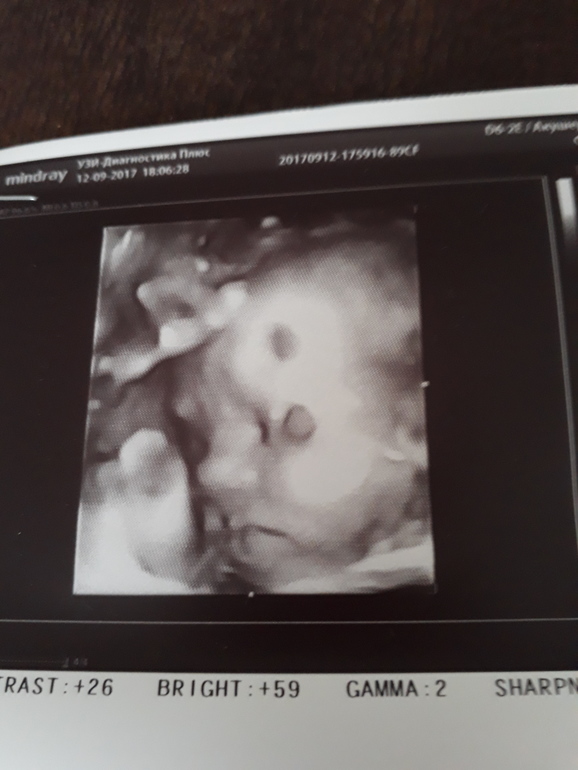

Ну вот вчера ездили на УЗИ,все хорошо весим мы 2000кг,на фото копия папуля.Ждем встречу с нашей принцеской.